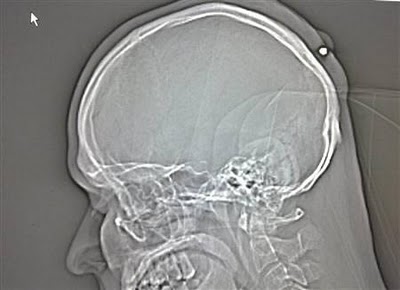

2. Orang yang ditembak di kepalanya,tetapi baru mengetahuinya 5 tahun kemudian.

Seorang lelaki yang tinggal di Jerman hidup dengan normal dan baik-baik saja selama lima tahun tanpa menyedari dia telah ditembak di kepala.Peluru kaliber 0,22 ditemui ketika lelaki itu pergi ke dokter untuk memeriksanya.Yang dia ingat adalah bahwa dia telah menerima pukulan ke kepala pada tengah malam di sebuah parti Tahun Baru “di tahun 2004,atau 2005″,tapi terlupa tentang hal itu kerana dia “sangat mabuk”.